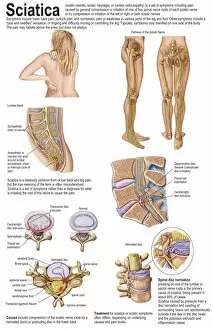

The central nervous system, the intricate network that governs our every thought and movement, is a marvel of complexity. From the delicate cerebellum tissue to the detailed light micrograph capturing its essence, we are reminded of its importance in maintaining balance and coordination. Anatomy comes alive as we explore the human brain from an inferior view. The intricacy of brain fibers is revealed through DTI MRI scans like C017/7099 and C017/7035, showcasing their vital role in transmitting information throughout this extraordinary organ. Artistic renderings bring us closer to understanding the medulla oblongata's significance within the brain. Its portrayal in various artworks allows us to appreciate how it controls essential functions such as breathing and heart rate. As we delve deeper into studying the central nervous system, models of the human brain provide invaluable insights into its structure and organization. Lateral views reveal countless regions responsible for cognition, emotion regulation, sensory perception, and motor control. Microscope slides offer glimpses into nerve cells' intricate architecture—a testament to their ability to transmit electrical signals at lightning speed. Meanwhile, glial stem cell cultures captured under a light microscope remind us of their crucial role in supporting neuronal function. Finally, artistic representations unveil the limbic system's enigmatic nature—an interconnected web responsible for emotions and memory formation. These captivating artworks allow us to visualize this complex network within our brains. Exploring these hints provides a glimpse into the awe-inspiring world of our central nervous system—the very foundation upon which our thoughts, actions, memories reside—reminding us just how remarkable our brains truly are.